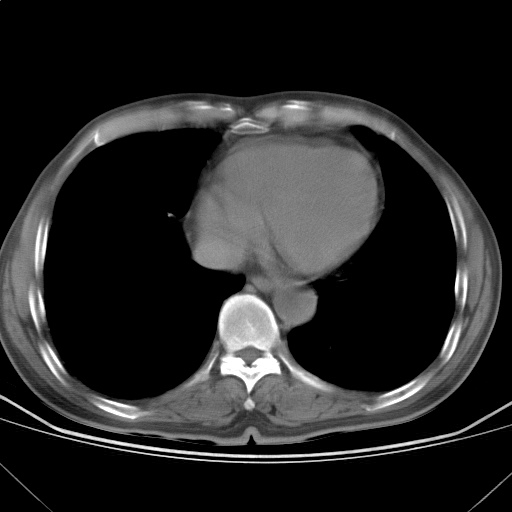

以下是引用随光逐影在2009-5-1 13:53:00的发言:[br]考虑为:1)两肺血行播散型肺结核;2)右肺下叶炎症感染。3)右侧胸膜增厚。